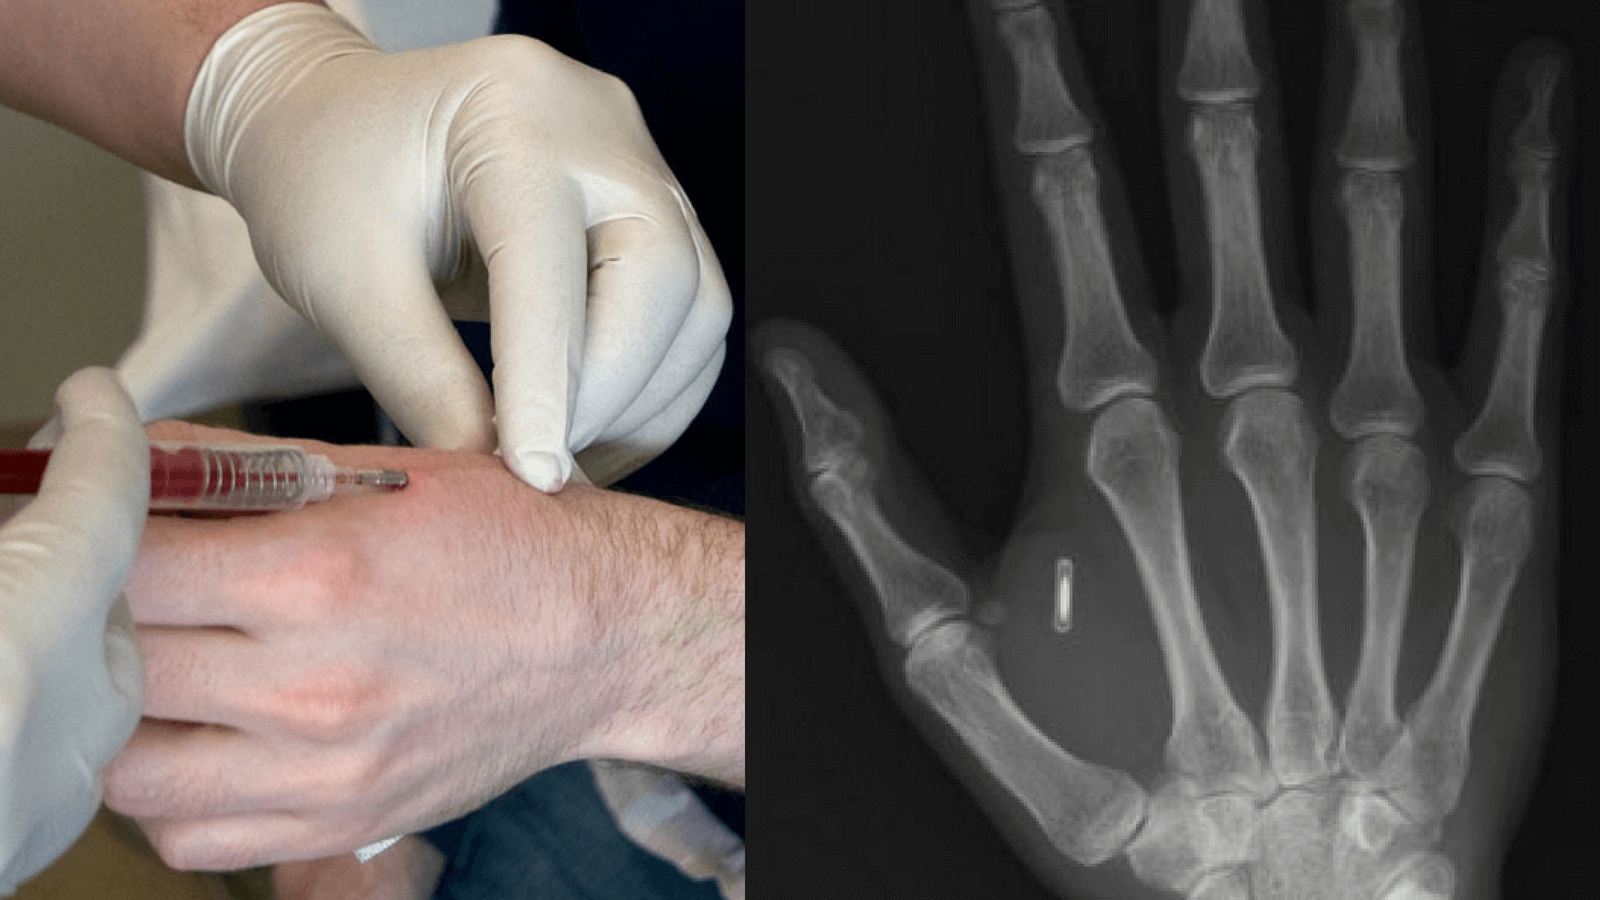

In Which Hand Does Aventurine Have The Chip?